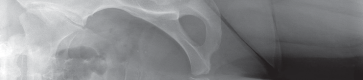

Thorough preoperative evaluation is mandatory. Plain radiographs remain the cornerstone of preoperative planning. An anteroposterior (AP) pelvis radiograph, along with AP and lateral radiographs of the affected hip, are highly recommended. These images allow for the assessment of bone quality, joint space narrowing, osteophyte formation, and the presence of subchondral cysts.

Surgeons must strictly template the radiographs to determine optimal component size and precise component position. The primary goals of templating are the restoration of the anatomic center of rotation, the reproduction of native leg length, and the re-establishment of femoral offset. Failure to restore offset can lead to abductor laxity, increasing the risk of instability and gait abnormalities. Occasionally, advanced imaging such as a computed tomography (CT) scan or magnetic resonance imaging (MRI) is indicated. These modalities are particularly useful to assess severe acetabular bone loss, large subchondral cysts, and complex three-dimensional deformity in developmental dysplasia during primary or revision total hip replacement.